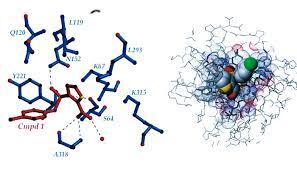

قیمت: 58٬000 تومان - دسته بندی فایل: پاورپوینتپاورپوینت الگوریتم های ژنتیک

فروش ویژه پاورپوینت حرفه ای الگوریتم های ژنتیک با تخفیف استثنایی فقط 92 هزار تومان تعداد اسلاید: 49 اسلاید